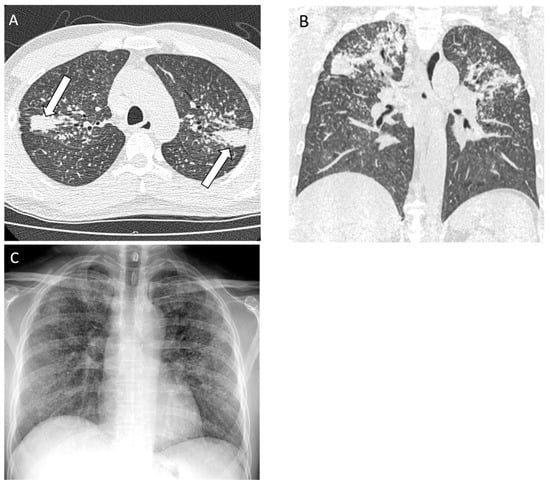

Figure 8.

A 62-year-old non-smoking male with metal vapor exposure in the workplace was diagnosed with non-fibrotic hypersensitivity pneumonitis on surgical lung biopsy. (A) CT of lung bases demonstrates diffuse ground glass abnormality posteriorly (white circle); (B) follow up CT 6 months after being removed from the workplace demonstrates compete resolution of the opacities; (C) chest radiograph shows a subtle increase in lung density at the bases (asterisks) with relatively preserved lung volumes.